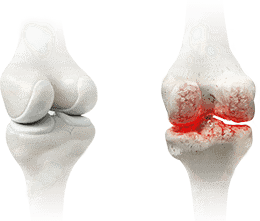

Las lesiones pueden variar en complejidad, pero se pueden agrupar en dos tipos: musculares y articulares. Esguinces, desgarros, osteoartritis crónica. Los riesgos son inevitables si no te proteges a tiempo.